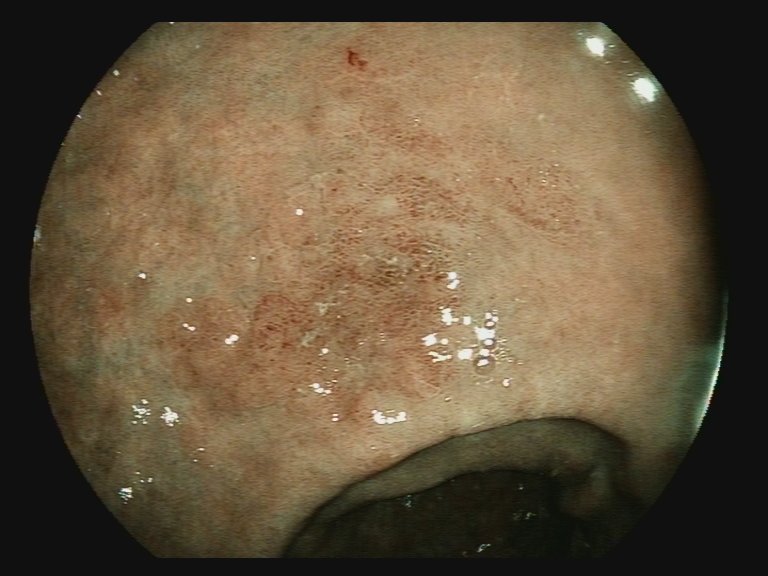

📢 March 2026 Issue #ACGCRJ 📷: Endoloop assisted hot snare polypectomy of a large brunner gland hamartoma in distal duodenum using colonoscope.🔦 🔗journals.lww.com/acgcr/pages/cu… @DushDahiya @DaniyalAbbasMD @AmCollegeGastro